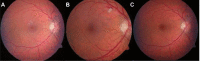

Ocular side effects of biological agents in oncology: what should the clinician be aware of?

During the last 20 years, biologicals have become increasingly relevant in oncologic therapy. Depending on the medication used, there are different profiles of ocular side effects. Although these can be present in up to 70% of patients, they are generally underreported in the literature. Therefore, the pathophysiological details of their development are often poorly understood. Herein we attempt to identify groups of biologicals to which a specific side effect profile can be assigned. We also tried to capture all relevant side effects and therefore conducted several database investigation including Medline, Cochrane library, and the drugs section of the US Food and Drug Administration (FDA), using the following search strings: "name of biological agent (both generic and commercial names)" AND "eye" OR "ocular". If we found a side effect that has been associated with a drug, we researched Medline using the following search string: "name of biological agent" (both generic and commercial names) AND "term for the specific side effect". Due to the wealth of material we report only the drugs that are approved by the FDA.